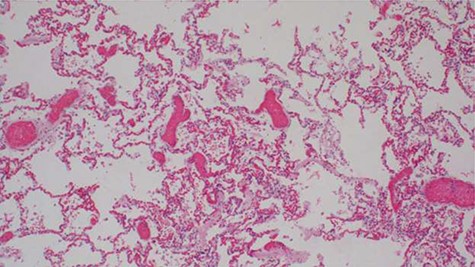

Histopathology analysis of the lung specimens revealed mixed chronic inflammatory infiltrates associated with pulmonary vascular thrombosis and areas of extensive necrosis (Figs 3 and 4). Bowel tissue sections revealed severe ischemic necrosis and mesenteric vessel thrombosis (Fig. 5). Thus, the primary causes of death were ruled to be ischemic colitis and pulmonary thrombosis due to COVID-19. The underlying disease conditions contributing to the cause of death being hypertensive heart disease, diabetes mellitus and septicemia.

Histopathology of lung tissue showing mixed chronic inflammatory infiltrates and vascular thrombosis (hematoxylin and eosin ×100).